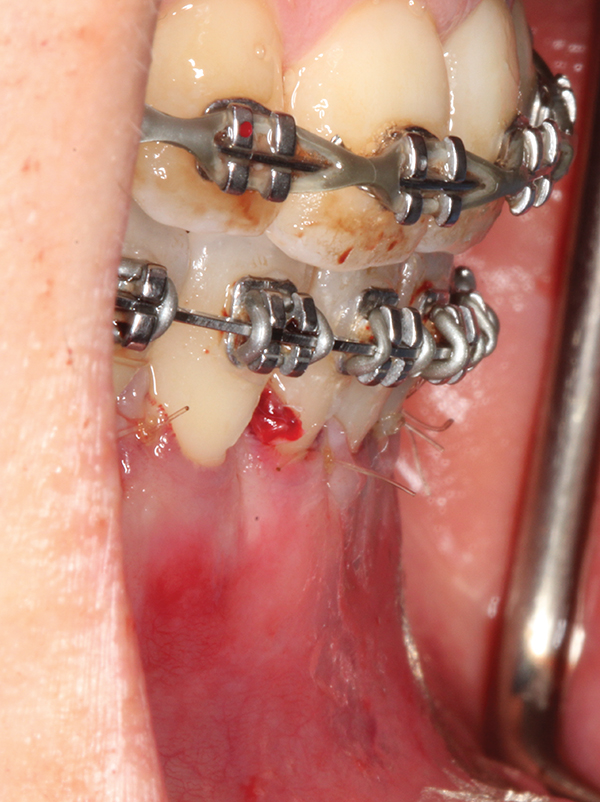

Fig 2. Full-thickness flap reflection. Note

dehiscence and fenestrations throughout. Orthodontic walls are limited to nonexistent.

Figure 2